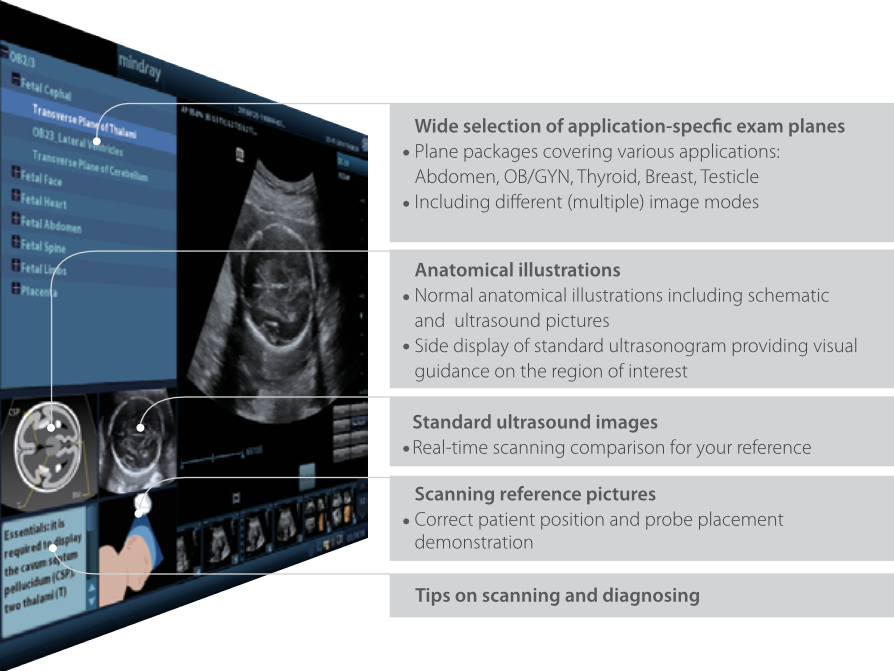

iScanHelper

Herramienta formativa integrada y exclusiva para que los usuarios comprendan y conozcan el uso de las ecografĂas. iScanHelper incluye ilustraciones anatĂłmicas, imĂĄgenes por ultrasonido estĂĄndar, imĂĄgenes de exploraciones de referencia y sugerencias para realizar exploraciones eficientes.